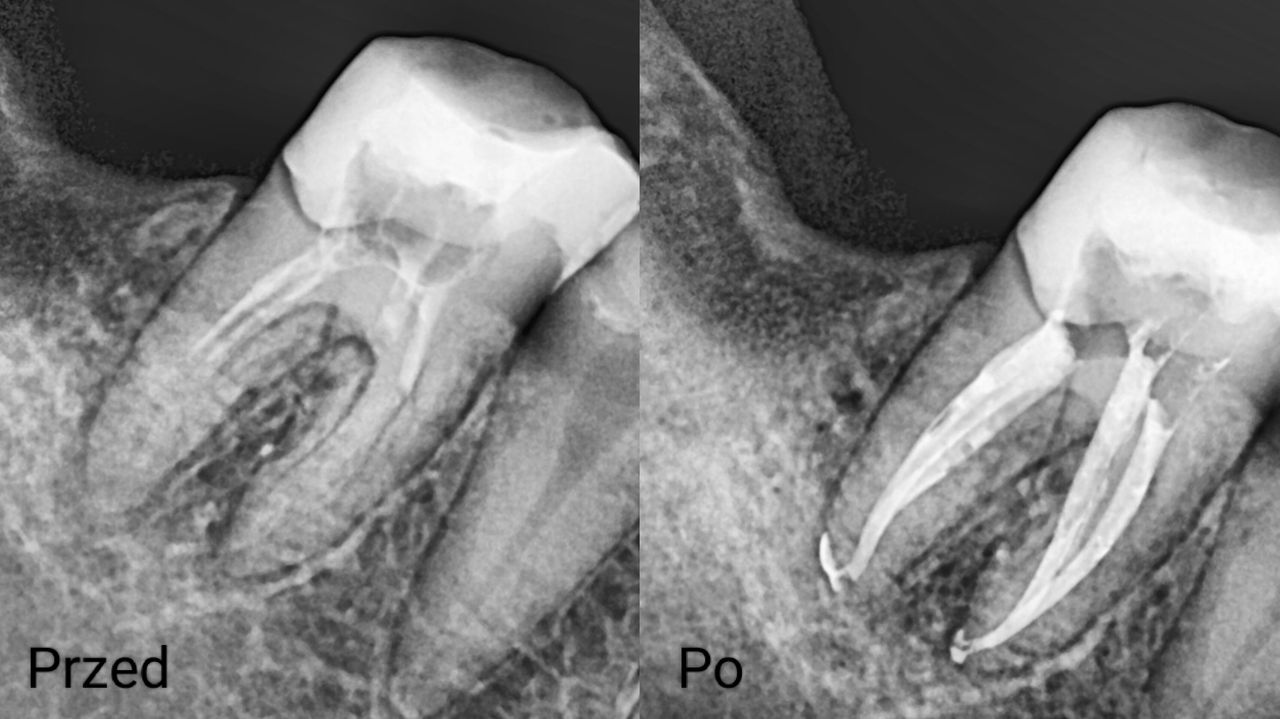

Na co dzień zajmuję się głównie stomatologią zachowawczą oraz leczeniem endodontycznym z wykorzystaniem mikroskopu. Wykonuję leczenie próchnicy i jej powikłań zarówno u dorosłych, jak i u dzieci. Zajmuję się również zabiegami higienizacji, wybielaniem zębów, leczeniem niepróchnicowych zmian szkliwa metodą ICON

Zdjęcia i filmy

Leczenie endodontyczne